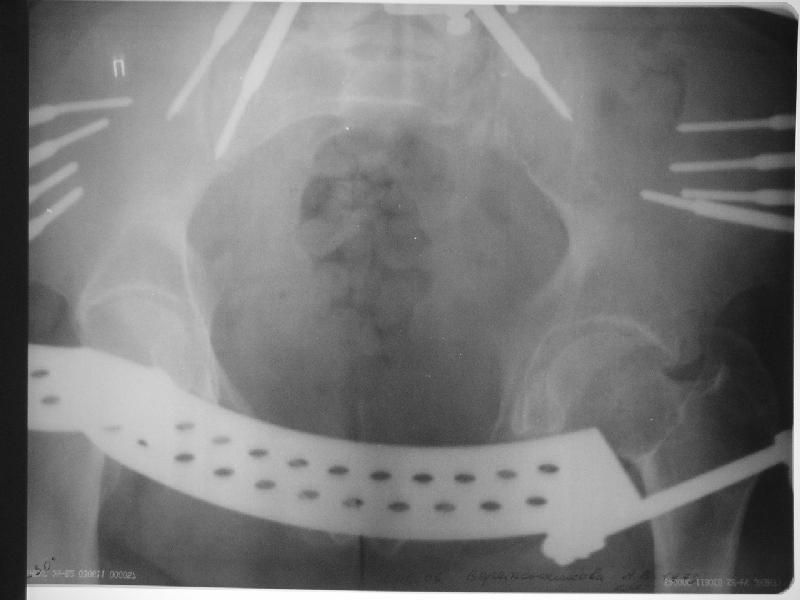

Прооперировали молодую девушку 32 лет спустя 9 мес после травмы.

Имелся стойкий болевой синдром, неопороспособность левой н/конечности, моторные и сенсорные нарушения в левой голени и стопе, патологическая подвижность левой половины таза. Первым этапом закрыто в аппарате исправили деформацию ( в течении 2,5 нед). Вторым закрытое введение илиосакральных винтов в крестец (канюллированные 7,2 мм Chm) + туннелизация зоны псевдоартроза спицама Киршнера, реконструкция передних отделов таза, накостный остеосинтез . Аппарат частично демонтирпован, оставлена "передняя рама" После устранения деформации отмечен регресс неврологической симптоматики, уменьшение болевого синдрома. Интересующие вопросы: 1. Прогноз для сращения псевдоартроза крестца. 2. сроки нагрузки весом левой половины таза. Буду очень признателен за ваши мнения по этому поводу.A female 32 y.o. admitted to our unit 9 months after initial injury with pain, inability to bear weight at the left lower limb, sensor and motor disturbances in the left foot and tibia, with mobility of the left hemipelvis.At first closed reduction was performed by an external fixator within 2,5 weeks. After correction her pain decreased and some neurological progress was achieved. Now two iliosacral screws 7,2 mm were inserted, and anterior lesion was fixed by a plate. External fixator was partially unmounted, only anterior frame left in place.Images attached.How would you evaluate chances of healing of the sacrum with the current position?When would you allow weight-bearing of the left leg?THX in advance.

Мне нравится ваша закрытая репозиция девятимесячного ложного сустава, не знаю насчет туннелизации, но шурупы в 7.2 это серёзная конструкция. При стабильной фиксации крестец должен срастись, только я бы держал передний фиксатор до шести недель, костыли, а полную нагрузку разрешить через 12 недель.